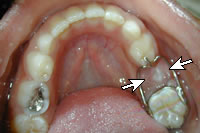

Hàm giữ khoảng cố định: Hàm này được lưu giữ nhờ các khâu nắn chỉnh răng hoặc các chụp thép có sẵn. Hàm giữ khoảng cố định có thể ở một bên hoặc hai bên. Ưu điểm: ít vướng, đắt tiền, hiệu quả hơn vì cố định. Nhược điểm: đòi hỏi vệ sinh tốt, phải chuẩn bị răng trụ, không phục hồi lại được kích thước dọc của khớp cắn, có thể bị bong hoặc gãy. Hàm này được chỉ định trong những trường hợp: mất một răng ở một bên, mất hai bên: trong trường hợp này hàm cần có các khâu nắn chỉnh và hàm có cấu tạo giống như cung lưỡi.